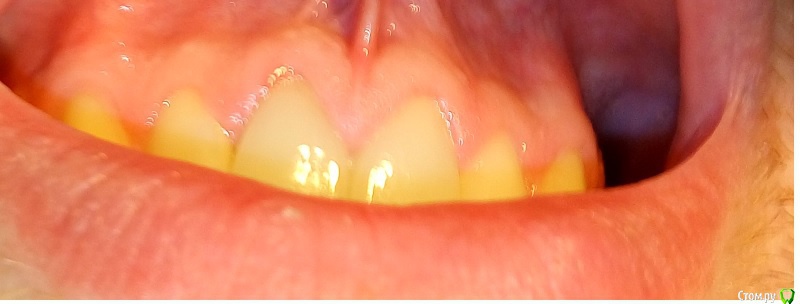

Opp80 Опубликовано 10 января, 2016 Автор Поделиться Опубликовано 10 января, 2016 (изменено) Чувствительность уменьшилась, но не прошла, далеко не прошла, пульсация периодическая и с отдачей в этот сосочек в периоды активного движения, т.е например поход в магазин, но не каждый раз (отметил на фото), у зуба есть небольшая подвижность так сказала другой врач на консультации, она сказала что возможно от того что врач постоянно лазил под десну, связки нарушаются, чтото типа того, но по симптоматике похоже на трещину, мой же врач на последней консультации, сказал может перфорация, и сказал делать ничего не будет больше, я же все мучаюсь, коронка поменяла свое положение появилась небольшая диастема за все время вмешательств.Прилагаю также понорамный снимок, и если кто глубоко заинтересуется КТ https://yadi.sk/d/TAjzSbIumYiyoP.S. когда попросил врача рентгены то он резко негативно высказался о том что я хочу спросить все на форуме, мол там не мастера, чему удивился чего бояться то, но снимки сказал даст, но они не понадобились я сделал КТ.Напомню, коронки стоят с 29 июля примерно, так и мучаюсь Изменено 10 января, 2016 пользователем Opp80 Ссылка на комментарий

Opp80 Опубликовано 16 января, 2016 Автор Поделиться Опубликовано 16 января, 2016 (изменено) Уважаемые врачи посмотрите пожалуйста такие десна были до установок постоянок (фото 1,2) и после 3,4Это с коронками чтото нето? Изменено 16 января, 2016 пользователем Opp80 Ссылка на комментарий